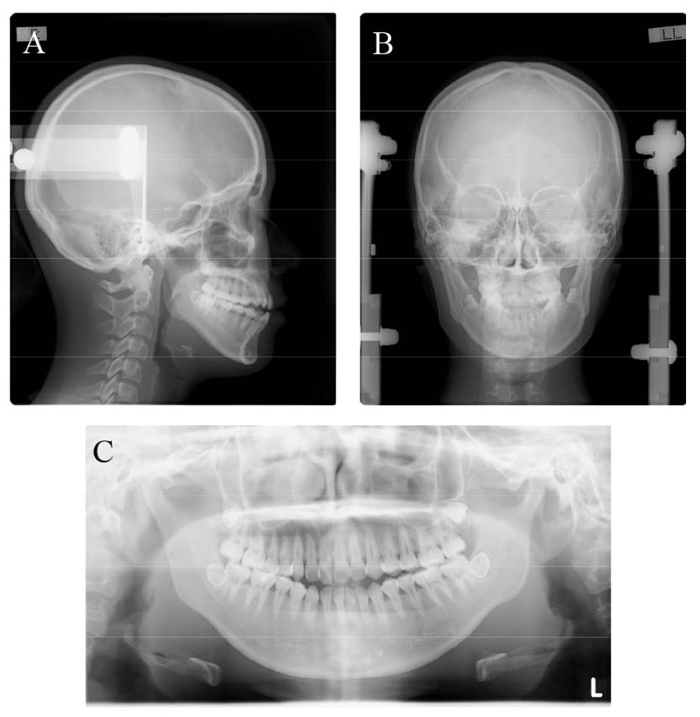

The patient was a girl aged 20 years and 5 months who came for orthodontic treatment with chief complaints of anterior open bite and facial asymmetry (Fig. 1). The patient had no relevant family history and no medical or dental history of dental trauma. She had a straight profile and severe mandibular deviation toward the left according to the mandibular deformation in addition to occlusal plane canting and transverse dental compensation. The soft tissue vertical reference line was constructed as the line perpendicular to the interpupillary line [14]. The maxillary dental midline and the mandibular dental midline were deviated 1.5 mm and 7.5 mm toward the left of the facial midline, respectively. The soft-tissue menton deviated 12.0 mm toward the left. Intraoral examination showed Angle Class III molar relationship on the right and Angle Class I molar relationship on the left with minor crowding of both dentitions. Overjet was 0.2 mm, and the overbite was –2.5 mm.

Panoramic radiography showed no horizontal or vertical bone loss and normal root length (Fig. 2). The cephalometric assessment showed a skeletal class I relationship (ANB angle, 3.2°) (Table 1) with a high mandibular plane angle (FMA, 35°) and occlusal plane angle (Occ plane to FH, 15.0°). The mandibular and maxillary incisor inclinations were normal (FMIA, 56.2°; U1-FH, 113.6°). Computed tomography (CT) imaging showed marked menton deviation to the left (13.5 mm) (Fig. 3 and Table 2) and dental asymmetry associated with occlusal plane cant (bilateral differences in tooth height: U3-H, 0.9 mm; U6MB-H, 3.3 mm). In addition, the bilateral differences in coronal ramus angle (coronal ramus angle, 10.3°) and ramus position (Rma-S, 13.6 mm) were significant [15].